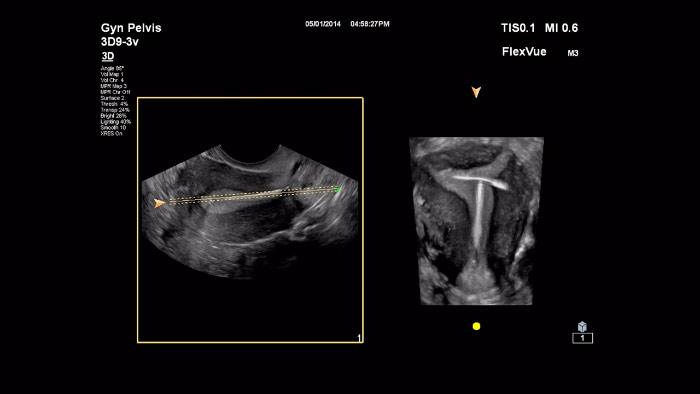

En este vídeo, el Dr. Michael Ruma presenta FlexVue, una herramienta de evaluación 3D avanzada de Philips. FlexVue permite visualizar con facilidad vistas anatómicas difíciles desde un punto de vista técnico a partir de volúmenes 3D, esenciales para el diagnóstico de enfermedades obstétricas/ginecológicas.

En este vídeo se describe MPR Touch, una función más intuitiva que los controles de MPR tradicionales. A diferencia de los mecanismos empleados para manipular un conjunto de datos de volumen de la MPR tradicional, MPR Touch permite realizar movimientos sencillos en la pantalla táctil para manipular todos los parámetros multiplanares y así producir la presentación de volumen 3D deseada.